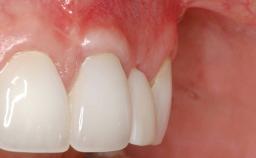

This case demonstrates that a connective-tissue graft in combination with a coronally positioned graft is an effective method of treating cases with peri-implant mucositis and an abutment-level sinus abscess. A 42-year-old man presented with a swelling adjacent to an implant crown at site 21. The swelling had been present for approximately three weeks and was constrained to the buccal and palatal gingival aspects of the implant. A discharge was noted on finger pressure, with localized gingival recession present on the mid- and distolabial aspects of the crown.

Soft Tissue Anatomy Intact Defective